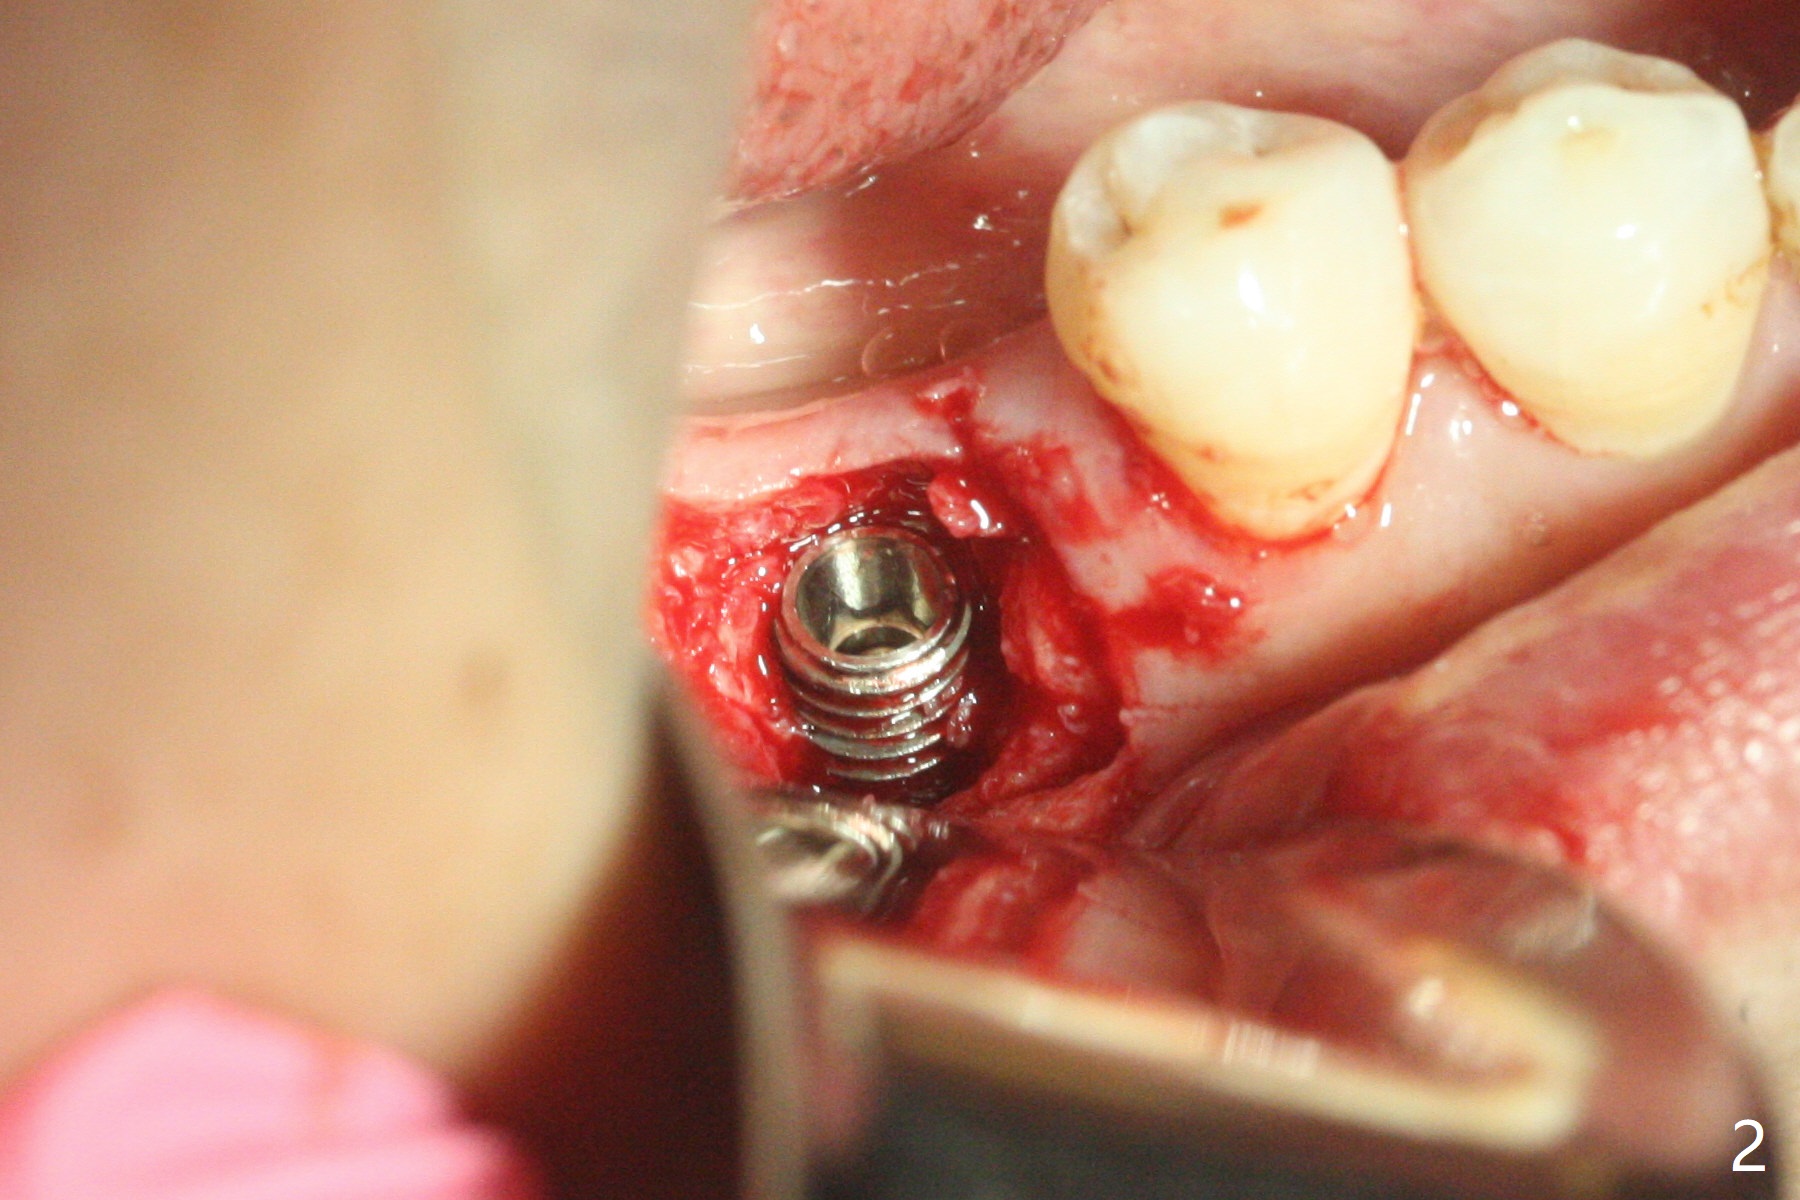

9个月,再次植骨7个月后,颊侧角化龈恢复正常,但是牙槽嵴伤口愈合有些异常(图一:*)。切开后显示螺纹暴露严重,由于整合,必须用环形刀才能取出植体,即刻抽血,植入粘性骨粉,充填植体所在位(图三:I)和颊侧缺损,覆盖PRF膜(x2),松弛切开后,缝合,树脂敷料保护伤口。失败可能原因:植体还偏大(4.5毫米;4毫米两段式五级钛或者3.5毫米一段式),坚硬舌侧骨板迫使植体颊侧移位(最后钻头应该与植体直径一样,适当再种深点)。临时牙冠不应该两周取出,树脂敷料好像更稳妥。